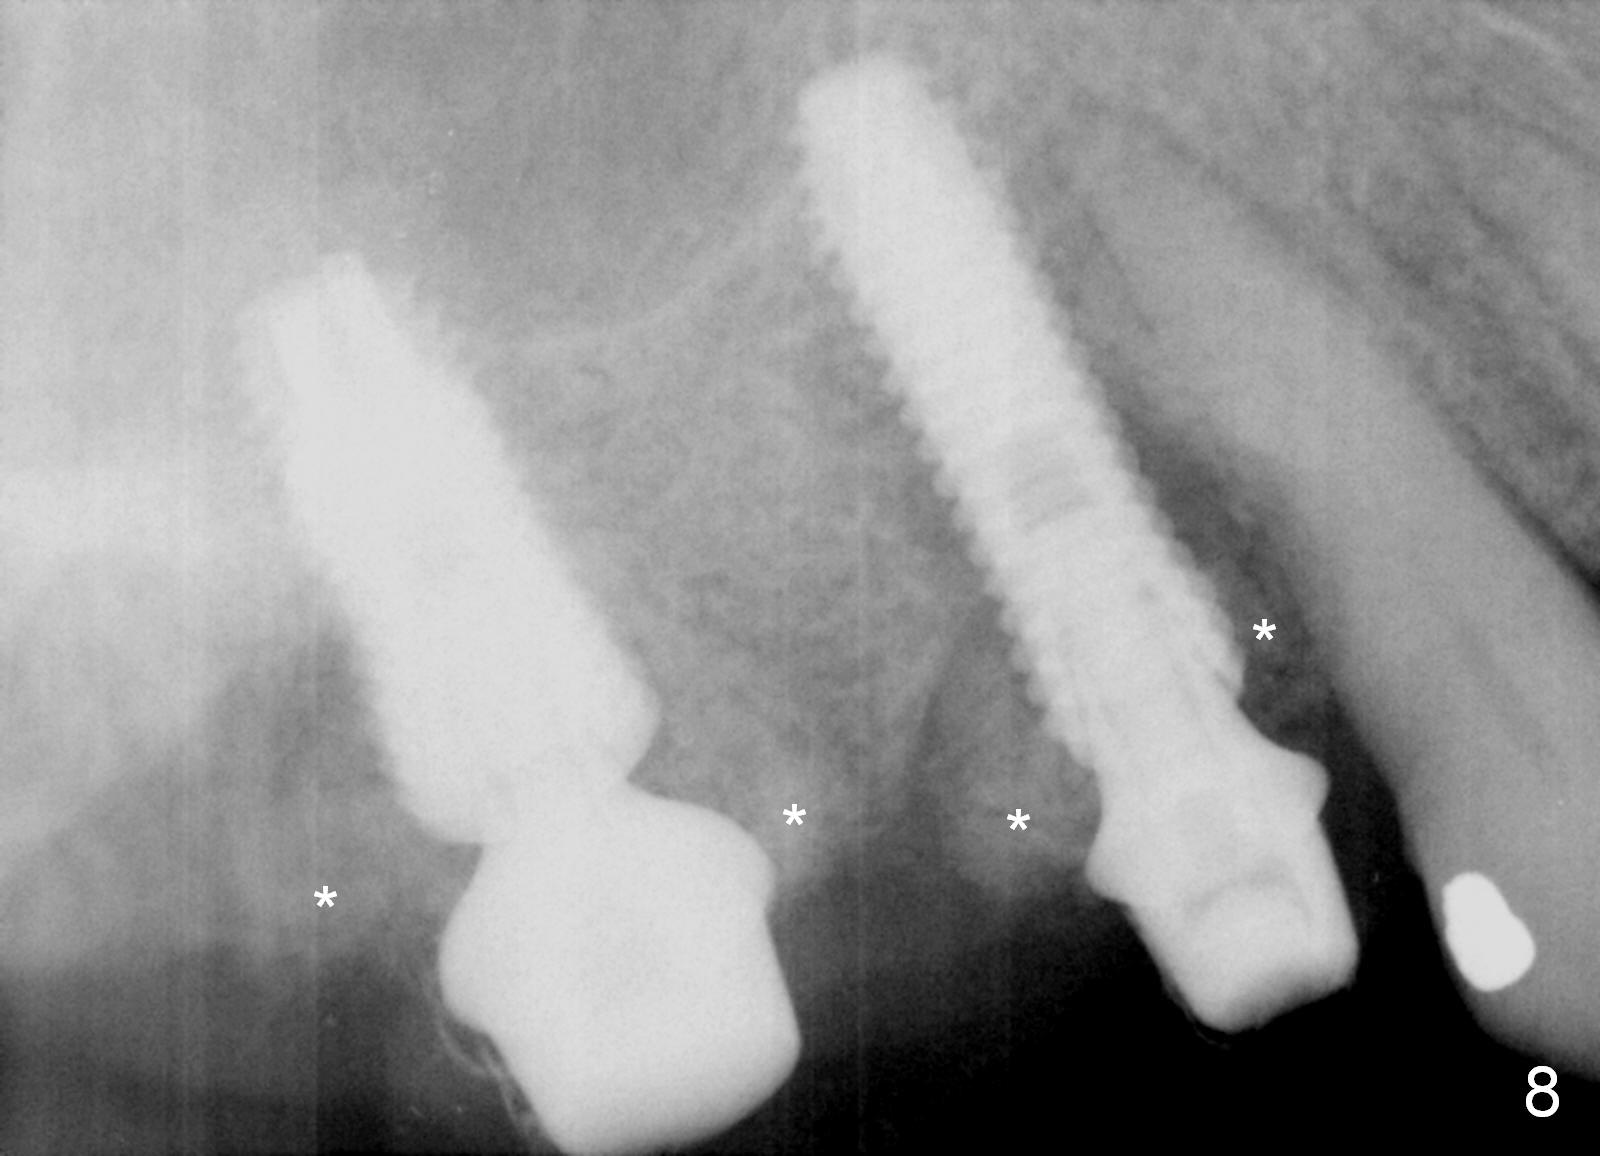

Preop photos show generalized gingival hyperplasia (hypertension med (Amlodipine, Calcium Channel Blocker), Fig.1 *), palatal (Fig.2<) and buccal (Fig.3 B) abscesses originated from the tooth #5. There is a smaller abscess buccal to the tooth #3 (not shown). After extraction, the buccal and palatal plates of the teeth #3 and 5 are found basically non-existent. When taps are placed, large socket defects are evident (Fig.4 *). In addition to sinus lift at #3 (Fig.5 black *), mineralized cancellous and cortical allograft (.5-1 and 1-2 mm) is placed around the implants with healing screws in place (white *). After the healing screws are removed and cemented abutments are placed, more allograft is packed (Fig.6-8 *). Closing the "dead" space in step may prevent immediately postop infection and peri-implantitis.